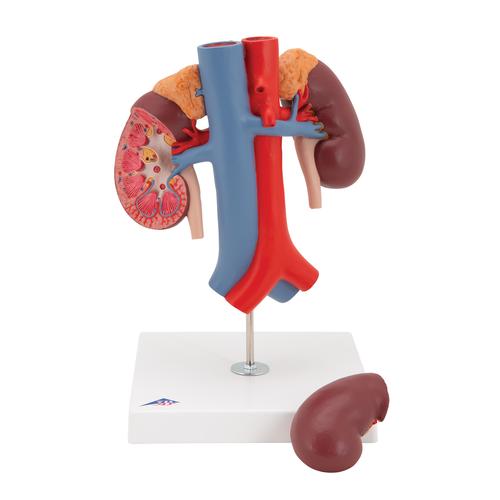

Эта модель в натуральную величину демонстрирует почки с надпочечниками, мочеточники, внутрипочечные сосуды и крупные кровеносные сосуды, расположенные в непосредственной близости от почек. Съемная передняя половина правой почки позволяет увидеть почечную лоханку, чашечки, корковый и мозговой слои почки. На подставке.